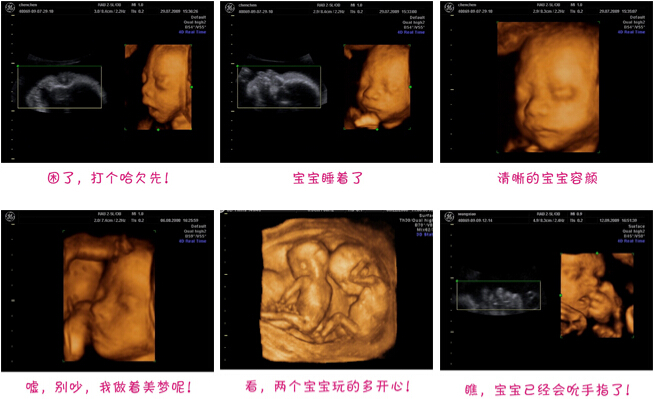

四维彩色超声诊断仪是目前较先进的彩色超声设备。其结果是:能够显示您未出生的宝宝的实时动态活动图像,或者其它人体内脏器官的实时活动图像。

同其它超声诊断过程相比,可以实时的观察人体内部器官的动态运动。临床医生和超声科大夫可以检测和发现各种异常,从心脏血管疾病到遗传性综合征。四维彩超能够多方位、多角度地观察宫内胎儿的生长发育情况,且可以为早期诊断胎儿先天性体表疾病和先天性心脏疾病提供准确的科学依据。

过去使用的B超设备只能检查胎儿的一些生理指标,而四维彩超还能对胎儿的体表进行检查,如唇裂,脊柱裂,大脑、肾、心脏、骨骼发育不良等情况,以便尽早的进行治疗,生个聪明健康的小宝宝。四维彩超能进行宫内写真,让准妈妈看到宫内宝宝的一举一动,亲身体会到宝宝的笑容相貌。